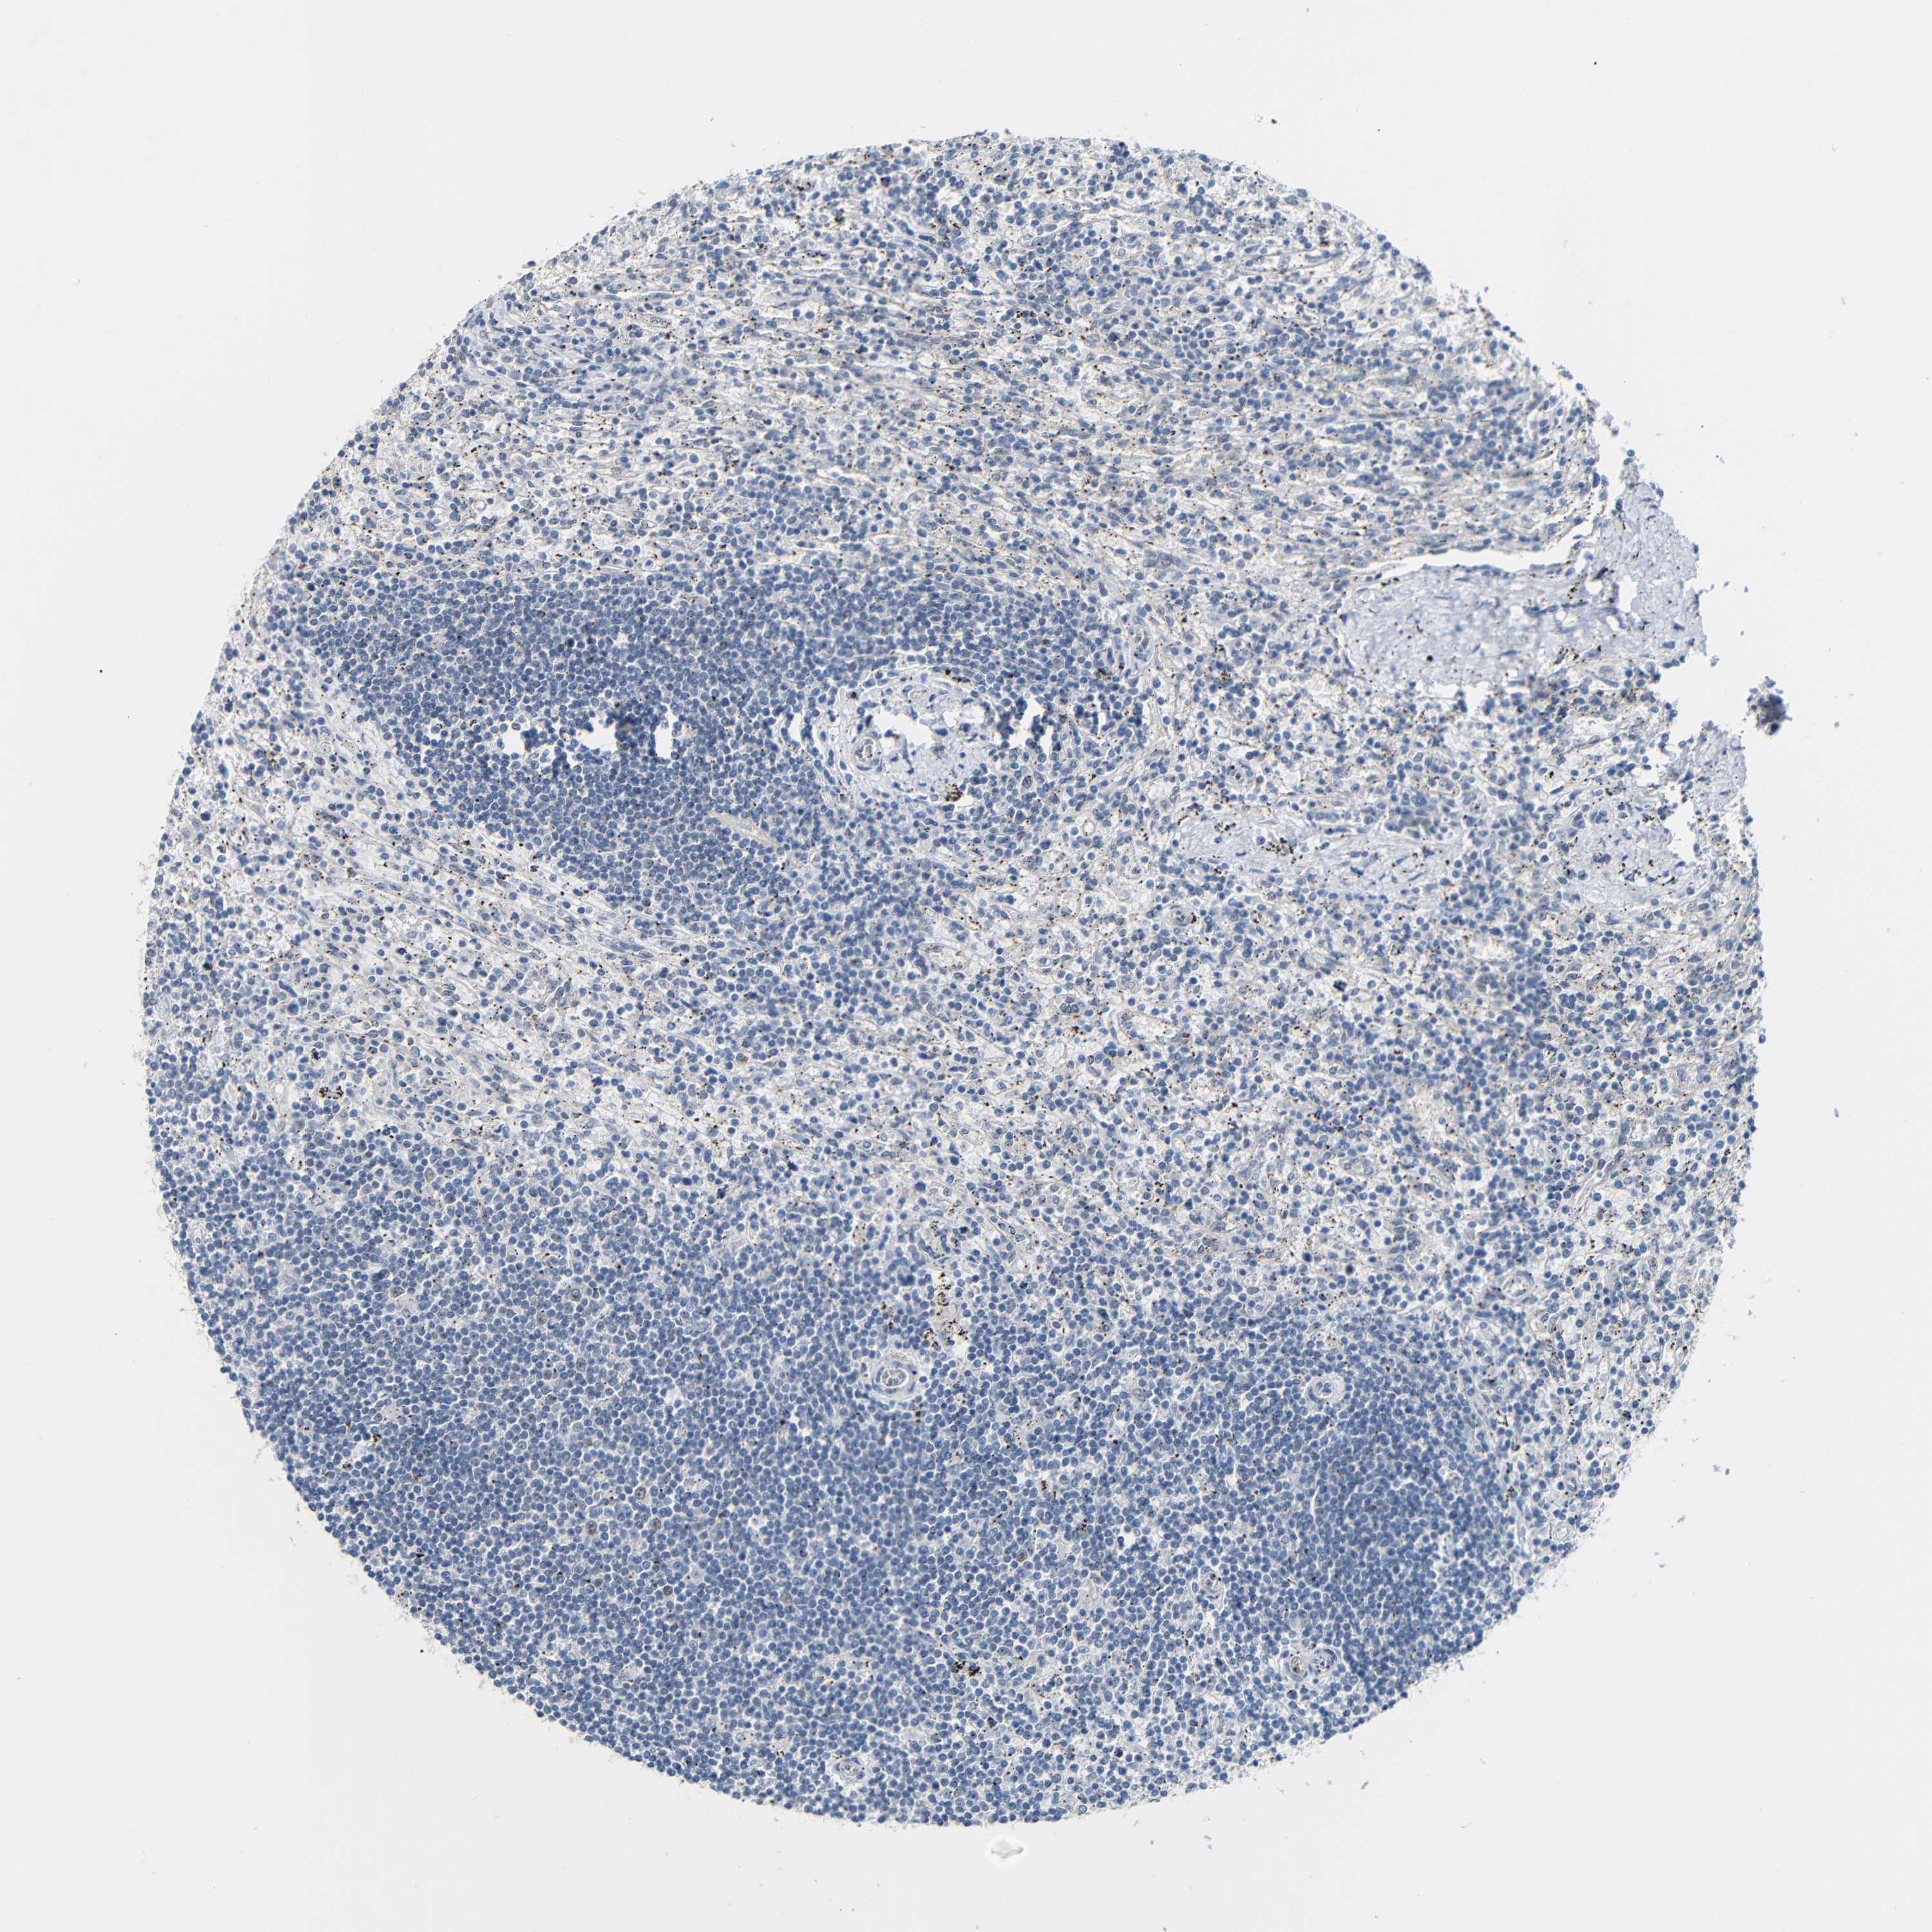

CANCER LYMPHOMA Show tissue menu

LYMPHOMA - Protein expressioni

A mouse-over function shows sample information and annotation data. Click on an image to view it in a full screen mode. Samples can be filtered based on level of antibody staining by selecting one or several of the following categories: high, medium, low and not detected. The assay and annotation is described here.

Each image is clickable and will lead to virtual microscopy that enables deeper exploration of all samples and also displays staining intensity scores, fraction scores and subcellular localization as well as patient and tissue information for each sample.

Antibody HPA013185

Staining

High

Medium

Low

Not detected

Intensity

Strong

Moderate

Weak

Negative

Quantity

>75%

75%-25%

<25%

None

Location

Nuclear

Cytoplasmic/membranous

Cytoplasmic/membranous,nuclear

Hodgkin's disease, NOS

Malignant lymphoma, non-Hodgkin's type, Low grade

Malignant lymphoma, non-Hodgkin's type, High grade